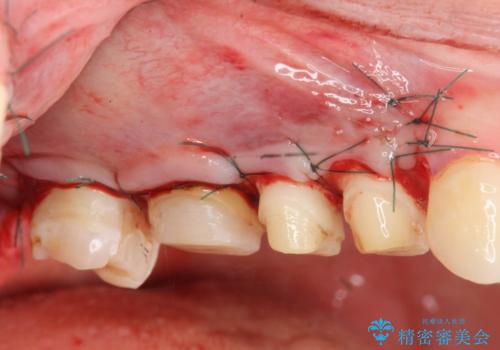

今回の治療では歯ぐきの問題を解決するため、歯周外科を行いました。

- 外科手術のため、術後に出血、痛みや腫れ、違和感を伴います